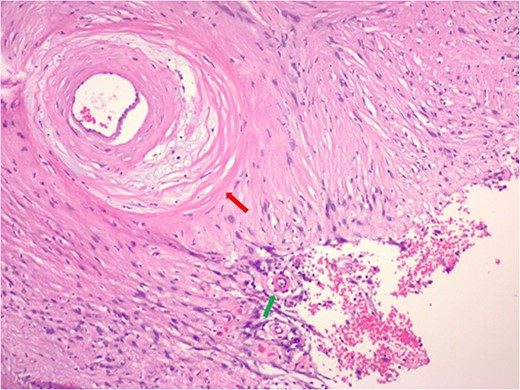

The pathology demonstrated an Ancient Schwannoma (see Fig. 3) with an adjacent ganglioneuroma (see Fig. 4). Because of the benign nature of this tumor, no further workup was required.

Hematoxylin and eosin stain pathologic slide of ancient schwannoma (green arrow) and adjacent ganglioneuroma (red arrow) with ganglion cell (yellow arrow).

Ganglioneuromas are defined as rare, benign neural crest cell tumors. These tumors are largely found along the distribution of the sympathetic chain. They are characterized as a mixture of ganglion and Schwann cells. However, the retroperitoneal location is relatively rare and more commonly found in the pediatric population. The majority of ganglioneuromas reported so far have been in the adrenal gland and the kidney [9].